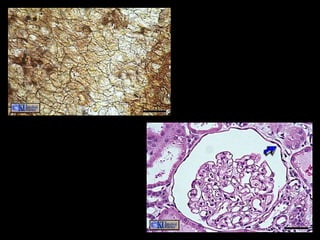

Shapes of Exocrine glands Branching Simple – single, unbranched duct Compound – branched. Shape: tubular or alveolar Tubular – shaped like a tube Alveolar – shaped like flasks or sacs Tubuloalveolar – has both tubes and sacs in gland

Shapes of Exocrineglands Branching Simple – single, unbranched duct Compound – branched. Shape: tubular or alveolar Tubular – shaped like a tube Alveolar – shaped like flasks or sacs Tubuloalveolar – has both tubes and sacs in gland